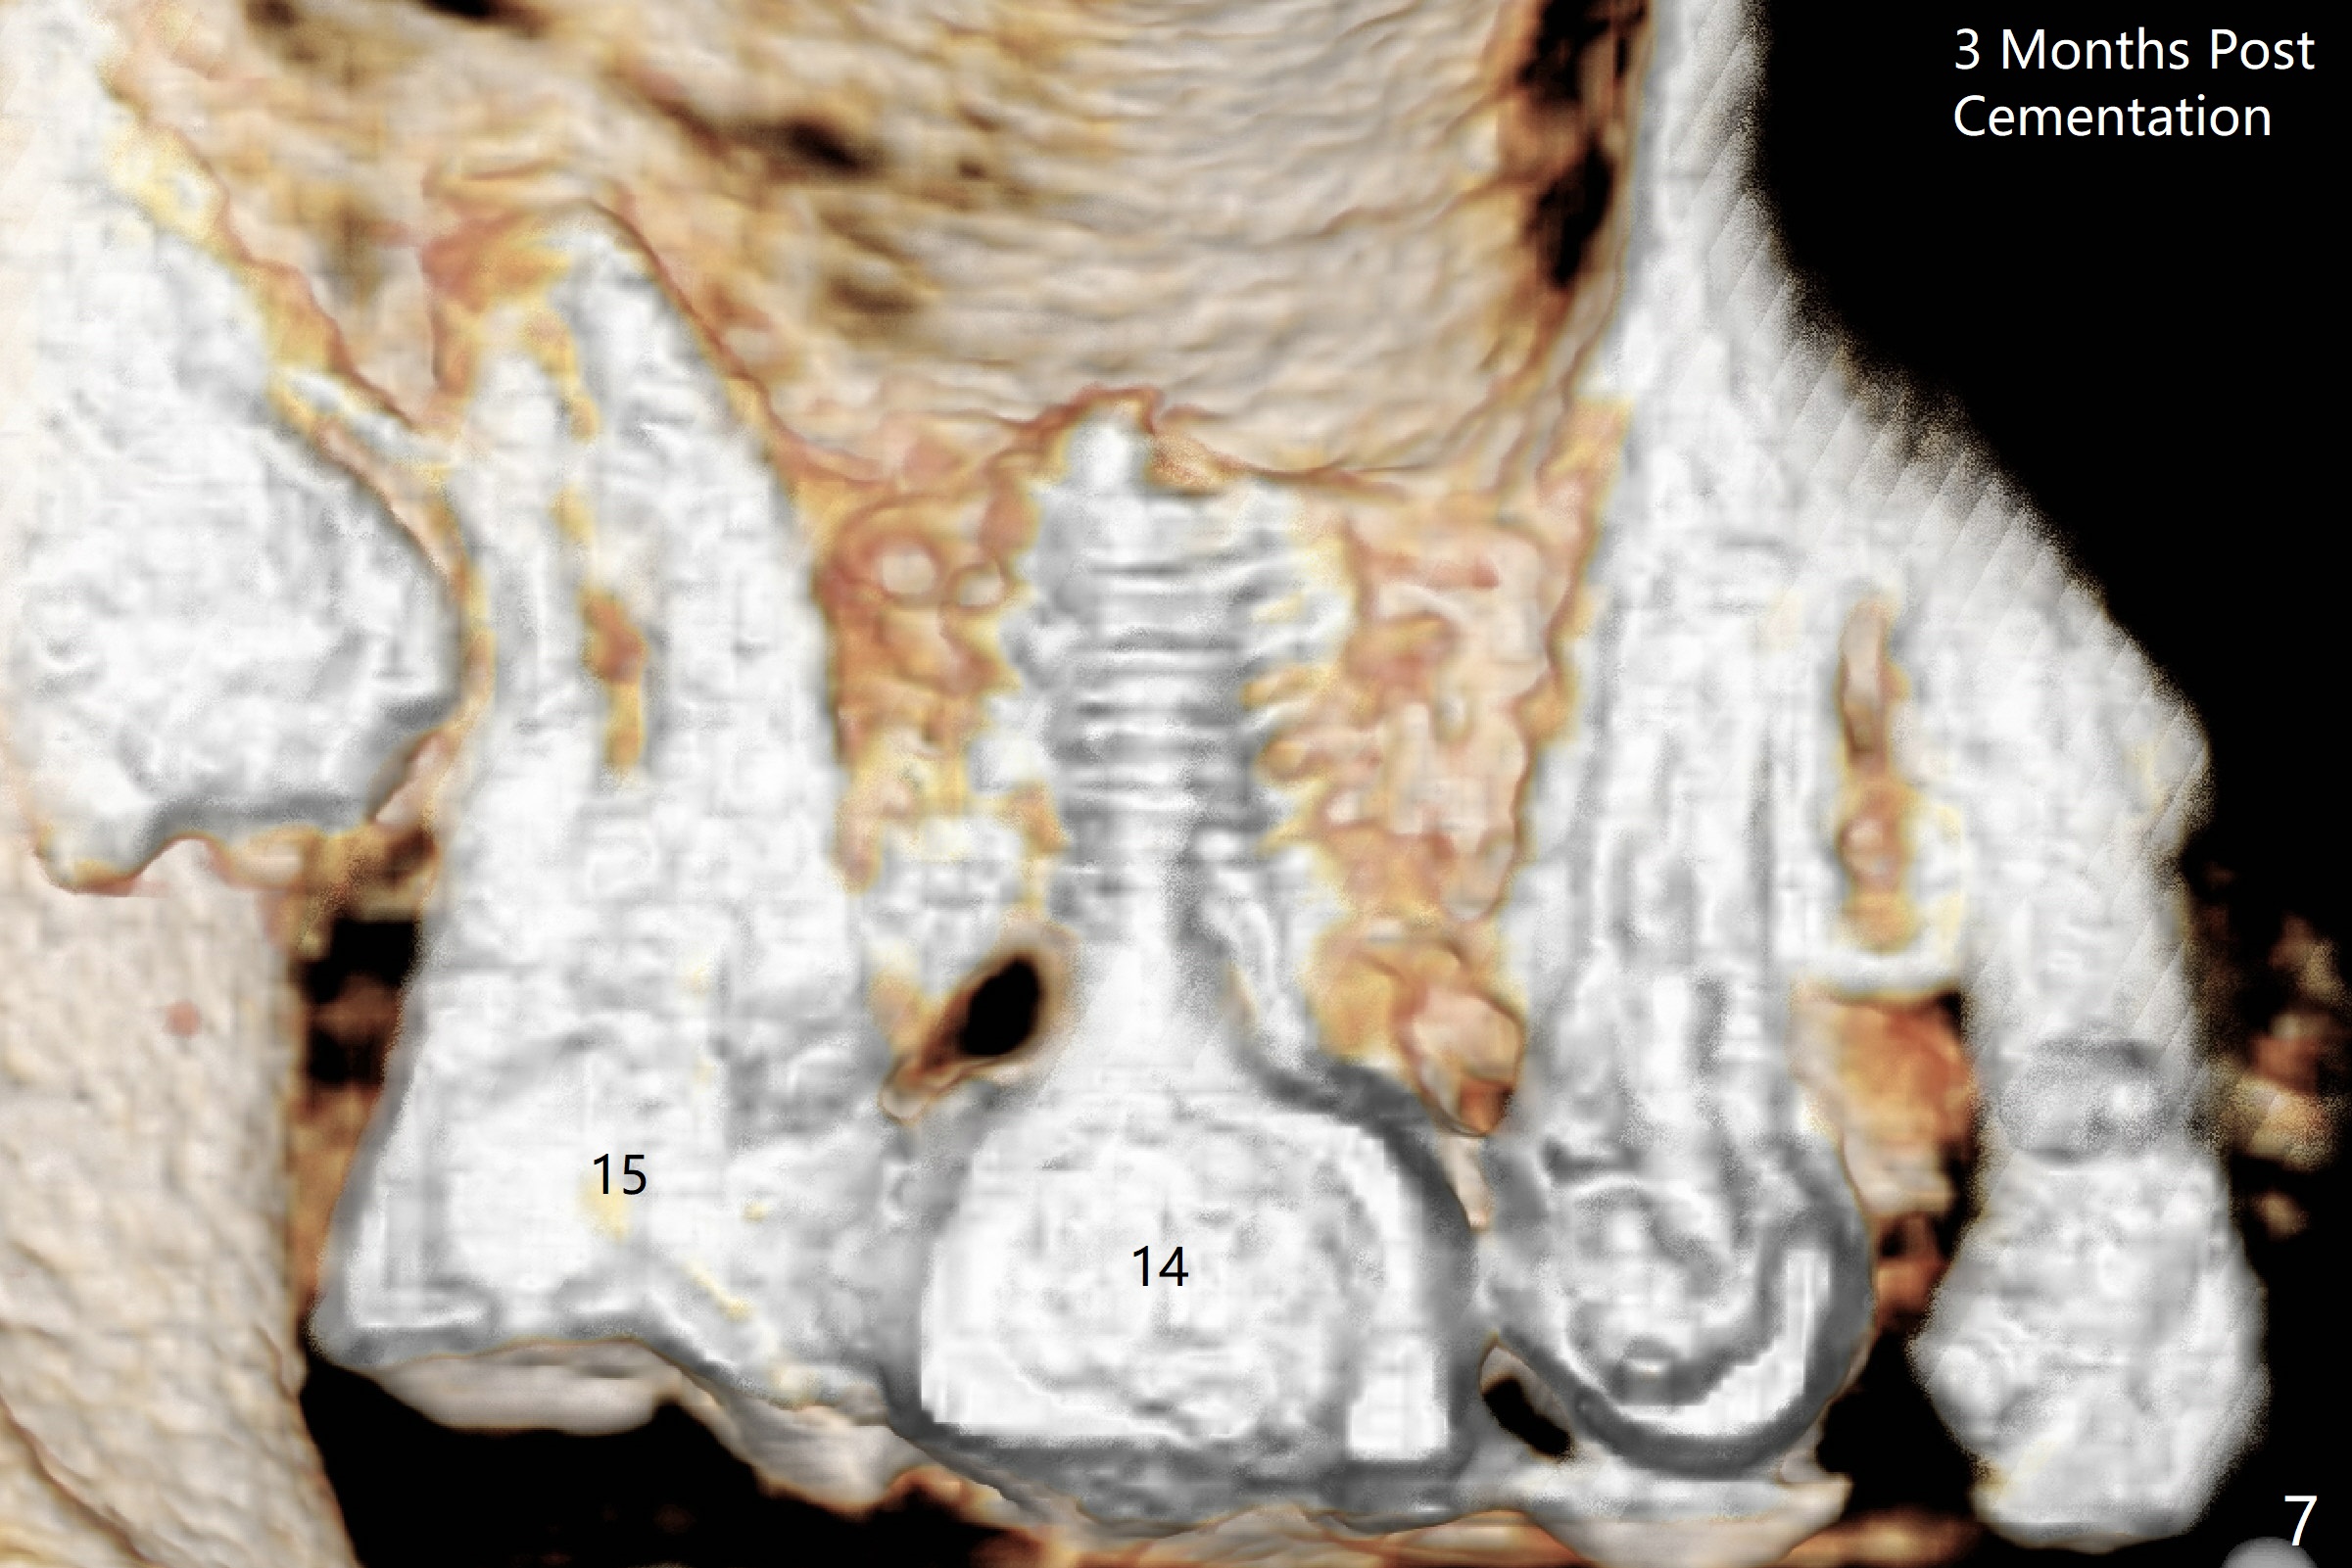

The ridge is wide at #14 11 months post socket preservation. Access and bone expansion (BEB) starts with Magic Split, followed by Magic Expanders 3.0, 3.8 and 4.3 mm from 8 to 9 mm for sinus lift. No bone is removed for osteotomy. Instead bone condensation occurs. After placement of a 4.5x11 mm dummy FC implant (Fig.1 with sinus lift (without bone graft)), a 5x9(2) mm Magicore (2 mm cuff) is placed with >55 Ncm with cuff margin at the gingival margin (Fig.2); a 5.5x3 mm solid abutment tries in. There is no occlusal clearance; trimming of the solid abutment will be needed. Later a healing screw is placed (Fig.3 *). There is no bone loss 5.5 months postop (Fig.4). A healing cap is placed without much tissue blanching. Instead a 5.5x3 mm solid abutment is placed; after height adjustment, impression is taken. A permanent crown is temporarily cemented 6 months postop (to rule out food impaction) and permanently re-cemented 7 months postop (Fig.5,6). CBCT taken 3-4 months post cementation shows that the implant threads are within the bone (Fig.7) and that the implant barely enters the sinus (Fig.8 *). That is significant since the patient has chronic sinusitis with thickened sinus membrane (Fig.9 *). The tooth #18 seems to have crazing line 10 months post cementation of the crown at #14 (overloading, Fig.10).